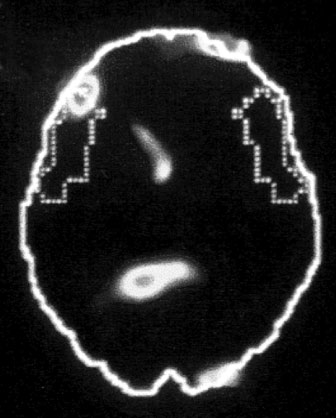

А. Правая лимбическая область

Б. Зрительная кора

В. Зона Брока

Изображение мозга в процессе переживания травмы. Светлые пятна в лимбической коре (А) и зрительной коре (Б) соответствуют повышенной активности мозга в этих участках. На снимке (В) видна значительно пониженная активность речевого центра мозга.

Сдвиг в одну сторону мозга

Снимки также показали, что во время этих живых болезненных воспоминаний у наших подопытных активировалась лишь правая часть мозга. В настоящий момент имеется множество научной и популярной литературы на тему различий между правым и левым полушарием. В начале девяностых мне доводилось слышать, что кто-то начал делить мир на людей с развитым левым (преобладает рациональное мышление, логика) и правым (интуиция, творческие способности) полушариями, однако тогда я не придал этой идее особого значения. Тем не менее наши снимки явно демонстрировали, что образы о пережитой травме активируют правое полушарие мозга, отключая при этом левое.